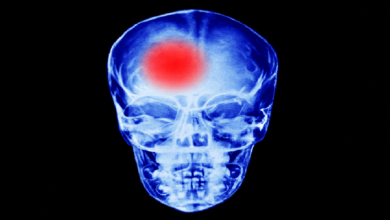

طبيب روسي يكشف أسباب الجلطة الدماغية في مرحلة الشباب

كشف الدكتور يوري سيريبريانسكي، أخصائي أمراض القلب، أسباب حدوث الجلطة الدماغية في مرحلة الشباب. ويشير الأخصائي في حديث إلى صحيفة…